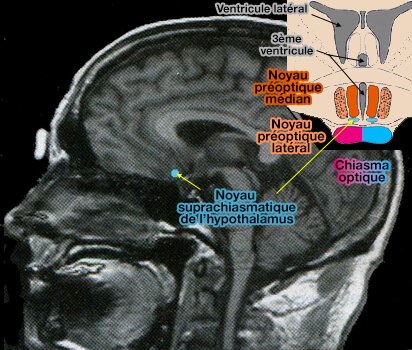

Les noyaux suprachiasmatiques de l’hypothalamus (NSC) sont considérés comme l’horloge maîtresse (« the master clock » de Stephan et Nuñez) des rythmes biologiques.

(Figure : vetopsy.fr)